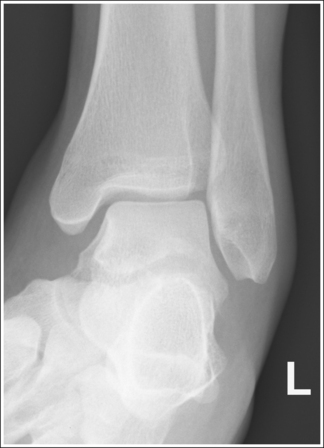

The ankle is demonstrated in an AP projection. The medial mortise (tibiotalar articulation) is open, and the distal tibia and talus are superimposed over the distal fibula by a small amount (0.125 inch [3 mm]), closing the lateral mortise (fibulotalar articulation).

• An AP projection of the ankle is obtained by positioning the patient supine on the image table, with the leg fully extended and the foot dorsiflexed until its long axis is placed in a vertical position (Figure 6-47). In this position, the intermalleolar line (imaginary line drawn between the medial and lateral malleoli) is at a 15- to 20-degree angle with the IR. The medial malleolus is positioned farther from the IR than the lateral malleolus.

• Detecting direction of ankle rotation. If the ankle was not positioned in an AP projection but is rotated laterally or medially, the medial mortise is obscured. When an AP ankle projection demonstrates a closed medial mortise, one can determine which way the patient's leg was rotated by evaluating the amount of tibia and talar superimposition of the fibula and the position of the medial malleolus. In external rotation, the tibia and talus demonstrate greater superimposition of the fibula and the posterior aspect of the medial malleolus (Figure 6-48) is situated medial to the anterior aspect (see Image 32). In internal rotation, the fibula is demonstrated without talar superimposition (see Image 33).

Mortise (15 to 20 degrees oblique): The ankle demonstrates 15 to 20 degrees of obliquity. The distal fibula is demonstrated without talar superimposition, demonstrating an open lateral mortise (talofibular joint), and the lateral and medial malleoli are in profile. The fibula demonstrates slight (0.125 inch [33 mm]) tibial superimposition.

• To obtain a mortise AP oblique ankle projection with accurate positioning, place the patient in a supine AP projection with the leg extended and the foot positioned vertically (Figure 6-52). The leg and foot are then rotated the desired amount. Make certain that the foot does not invert during rotation. While viewing the plantar surface of the foot, place your index fingers on the most prominent aspects of the lateral and the medial malleoli. Rotate the patient's entire leg internally (medially) 15 to 20 degrees, until your index fingers and the malleoli are positioned at equal distances from the IR (Figure 6-53). An imaginary line drawn between the malleoli (intermalleolar plane) is then aligned parallel with the IR. This rotation moves the fibula away from the talus to demonstrate an open lateral mortise.